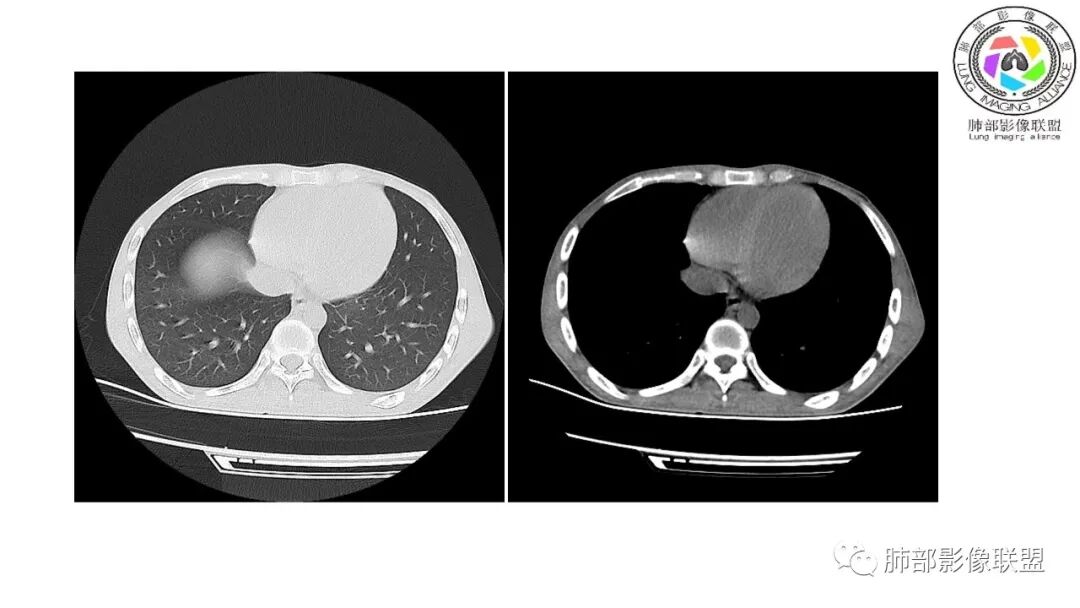

影像与临床:1.青年男性,HlV阳性,颜面部皮疹(未提供皮疹图像)、发热(高热),实验室CRP、PCT高,T-Spot阴性。2.右肺下叶空洞结节,壁厚不均,边界清楚,其内线状影,未见液平及钙化,未见卫星灶,纵隔淋巴结增大,双侧腋窝见增大淋巴结。心腔内低密度提示贫血可能。肝脾影增大,未见结节影及块影。腹膜后见多发增大淋巴结。

综合分析:本例肺部影像学改变并不具有特征性,空洞性病灶须与多种疾病鉴别,但年轻HIV阳性患者,高热,皮疹,肝脾增大,纵隔、腋窝、腹膜后见多发增大淋巴结等都强烈提示马尔尼菲篮状菌感染的可能性。